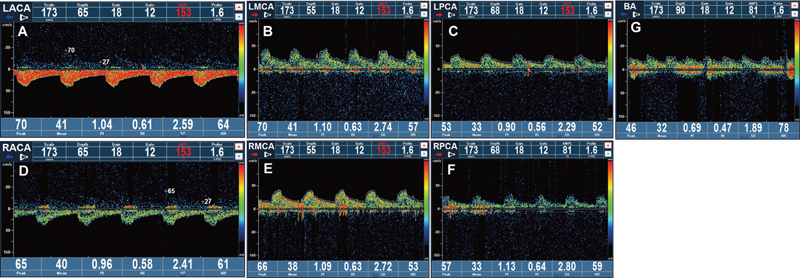

Case description: This article reports a case of an 82-year-old male patient who was diagnosed with VAF following a neck vessel ultrasound examination prompted by poor blood sugar control. The ultrasound revealed an abnormal course of the left vertebral artery, leading to the diagnosis of VAF.